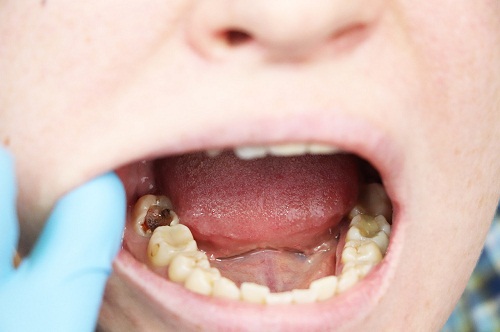

深龋齿则代表了龋病发展的进阶阶段,病变已经穿透牙釉质层,深入到了牙本质深层,甚至接近或达到牙髓腔(即牙神经所在的空间)。深龋会在牙齿表面形成明显的龋洞,这些洞腔容易嵌塞食物残渣,为细菌繁殖提供了理想环境,进一步加快龋坏进程。

深龋齿的临床表现则要明显得多。由于牙本质内含有大量牙本质小管,这些微细管道直接与牙髓相连,当龋坏到达这一层次时,牙齿会对各种刺激产生敏感反应。患者可能在饮用冷热饮料、进食甜食时出现明显疼痛,且这种不适感持续时间较长。当食物嵌入龋洞时,产生的压力会直接传递至牙髓,引发剧烈疼痛。部分患者甚至可能出现自发性隐痛,这往往表明牙髓已经受到严重影响。